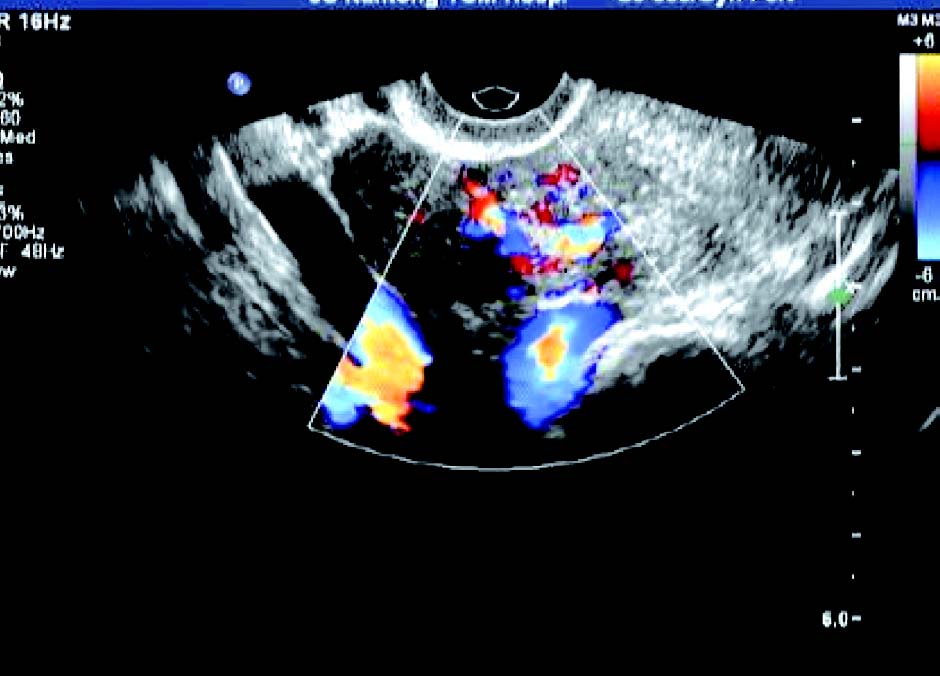

3. 黏膜下肌瘤

子宫内膜变形或缺损,内膜下肌层可见低回声结节突向宫腔,肌瘤完全突入宫腔时,宫腔内显示实性占位,但肌瘤与宫腔内膜间有裂隙,呈现“宫腔分离征”。CDFI 检测:瘤体周边呈环状或半环状血流信号,内部呈条状血流信号。